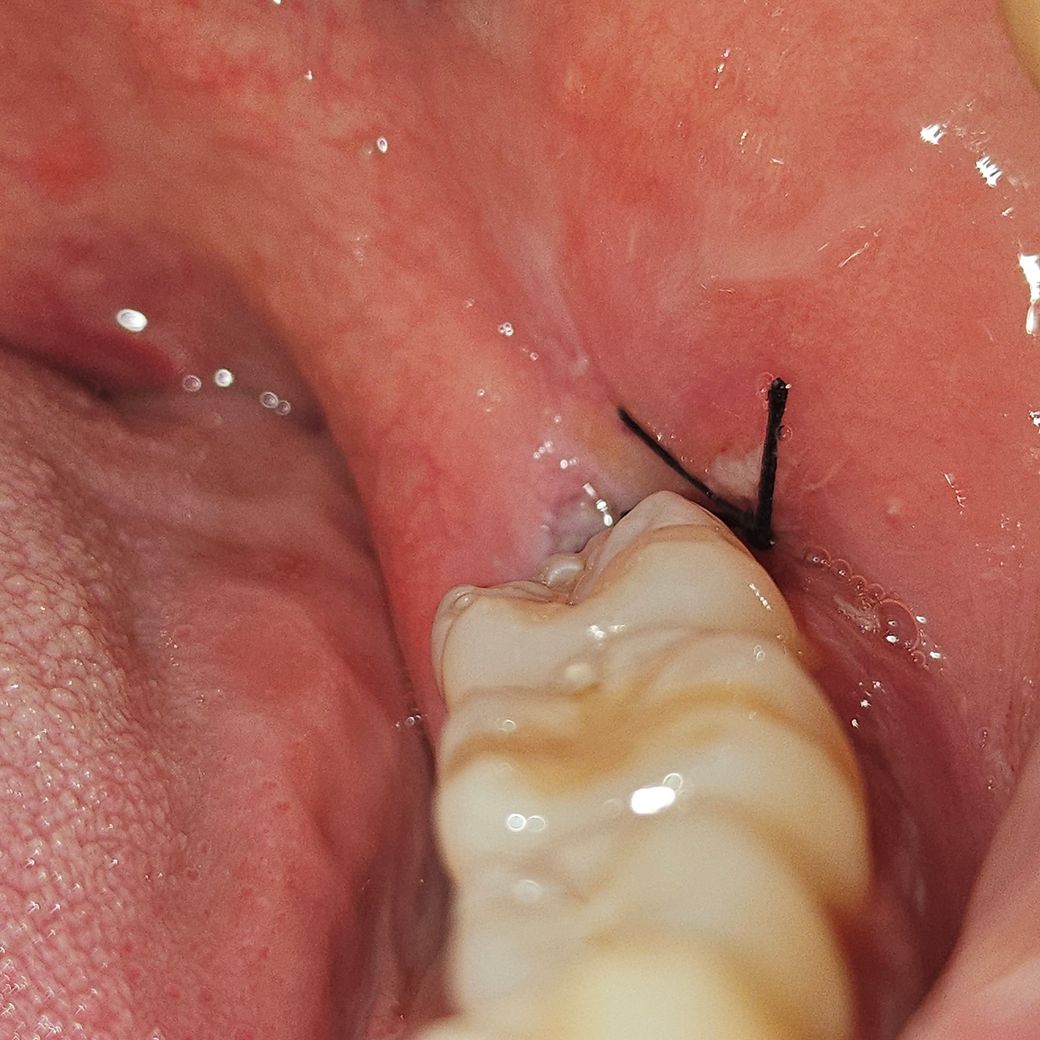

사랑니 발치 30시간째인데 이거 잘 아물고 있는건가요?

안녕하세요 사랑니 발치한지 30시간 조금 넘었는데 가만있으면 입에 피맛이 좀 돌아요 찾아보니까 혈병이 생기려면 진한 빨간색인거 같던데 저는 전혀 아니어서 잘 낫고 있는건지 궁금해요

• 2번 째 사진

사진상으로 보면 크게 문제가 잇는건 아닌거 같습니다. 실밥을 푸실때까지 음식물만 끼지 않도록 해주세요.

현재 사진상으로는 염증 등의 소견은 전혀 보이지 않습니다. 걱정하지 않으셔도 될 것 같습니다.

사진으로만 봤을경우 잇몸은 잘 아물고 있는것으로 보입니다.

사랑니 발치 후 30시간이 지난 상황에서 피맛이 나는 것은정상이며, 현재 잘아물고 있는 것으로 보입니다. 하지만통증 및 붓기가 있는 경우에는 치과에 방문하여 상태를 확인해보길 권합니다.